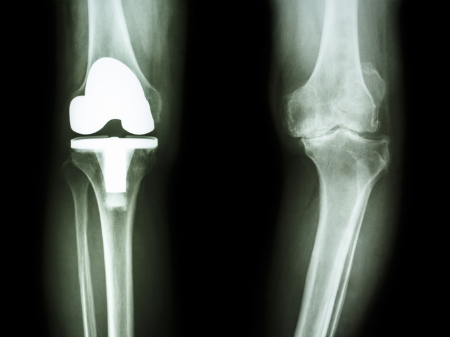

무릎 관절염의 진행 정도는 주로 'Kellgren-Lawrence 등급'(K-L Grade)으로 구분한다. X선 영상 결과를 바탕으로 관절 구조의 변형과 통증에 따라 크게 1~4단계로 구분한다.

무릎 구조가 변화돼 걷기조차 힘든 4기는 일상생활에 지장을 받을 정도로 증상이 악화한다. 이때는 보존적 방법이나 물리치료 같은 방법으로는 증상이 나아지지 않기 때문에 인공관절 등 수술이 불가피하다. 다만, 젊은 환자의 경우 휜 다리를 교정하는 근위경골절골술을 시행할 수도 있다.